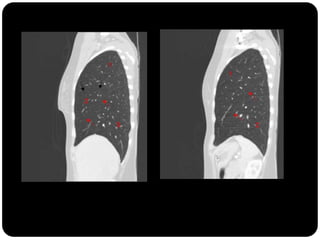

Vias aéreas

Traquéia       Fissuras interlobares: invaginações da pleura;

Brônquios

Bronquíolos

Alvéolos

Cisura maior esquerda mais

verticalizada

Pleura visceral

Fissuras

 Completas ou incompletas

 Em boa parte dos indivíduos elas são Incompletas.

 HORIZONTAL(completa em 25% dos pacientes): completas

lateralmente e incompletas medialmente, fundindo-se ao

lobo adjacente;

 OBLÍQUA: fusão é mais comum na parte póstero-medial

 Por que devo saber que as fissuras podem ser incompletas?

 R: fluxo colateral pelos canais de Lambert e poros de Kohns

pode permitir que o lobo permaneça aerado apesar da

completa obstrução de seu brônquio;

Canais de Lambert: vias aéreas acessórias entre bronquíolos

respiratórios ou espaços aéreos ventilados por outras vias

aéreas;

Poros de Kohn: poros cilíndricos que comunicam alvéolos

adjcentes;